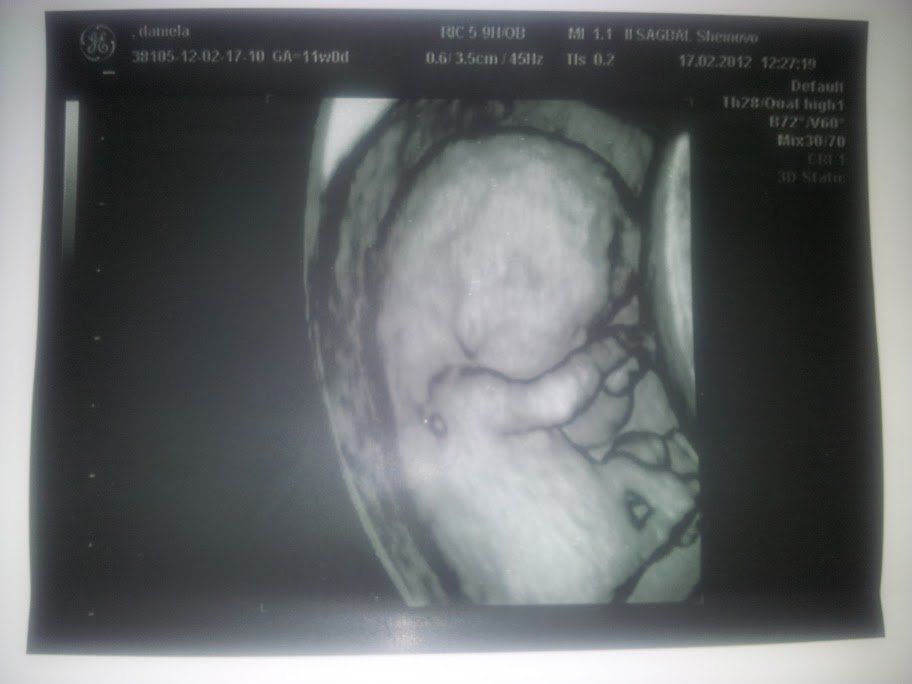

Дани-зай, чувствам, че и второто ще е мъж. мдаа. а ти разказваааай, разказвай  Hug Hug и бъди здрава, хау!